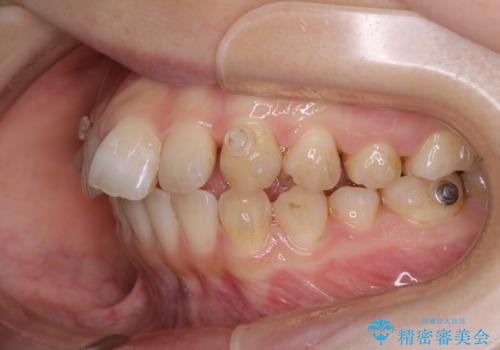

- 前歯の重なりが気になるとご相談にいらした方です。前歯のがたつきは奥歯の噛み合わせのズレが原因となっていたため、インビザラインFULLにて奥歯からしっかり治療していきました。

前歯のがたつきだけを治そうとした場合、噛み合わせは二の次なってしまう事が多く、せっかく綺麗になった歯並びも後戻りしやすくなります。

見た目だけでなく奥歯を移動させて噛み合わせの改善までが行えるのはインビザラインであるからこそです。奥歯の噛み合わせからしっかり機能させることで、長期間にわたって綺麗な歯並びを保ちやすくなります。